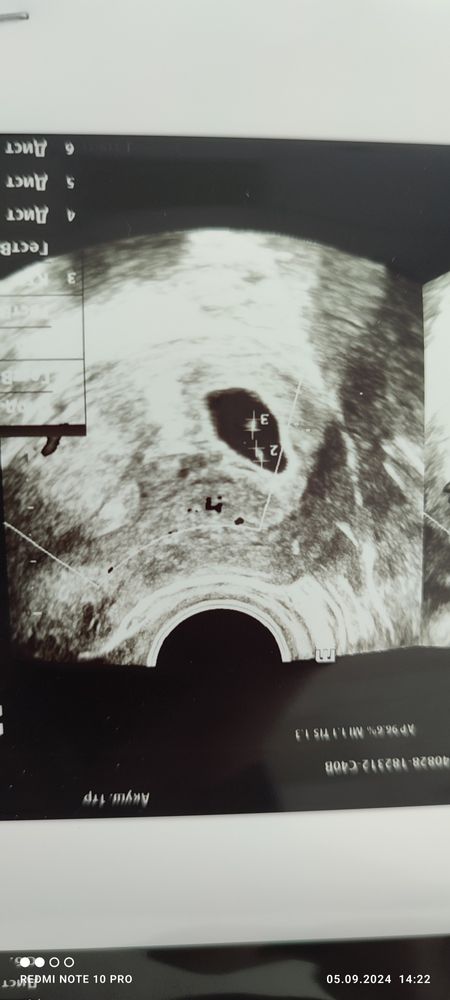

Марина, да, есть Изображение Изображение

Регина, так у вас здесь не многоплодная,а одно яйцо и большое уже 25*10*30 это свд 21,6 получается,а эмбриона вообще нет, поэтому и поставили что беременность неразвивается,так как пя большое уже и в таком пя эмбрион должен быть и сб, переделайте УЗИ в другом месте

Марина, а вот это УЗИ делали при поступлении на стационар. Если честно, то я в принципе не понимаю, почему они посчитали, что их там двое. У нас в семье и предпосылок к двойне то и нет ни у кого, но пишу, как сказал врач. Завтра пойду на еще одно УЗИ. Изображение

Регина, в этом пя у вас как-будто два эмбриона,но плодное яйцо одно,если одно плодное яйцо на двоих,то хгч не должен падать,так как хгч вырабатывает оболочка плодного яйца,это когда два плодных,одно перестает развиваться,а второе растет, возможно хгч и может снижаться,а с одним пя не должно,короче все странно,надо мнение третьего экспертного УЗИ,а по месячным какой срок у вас ?